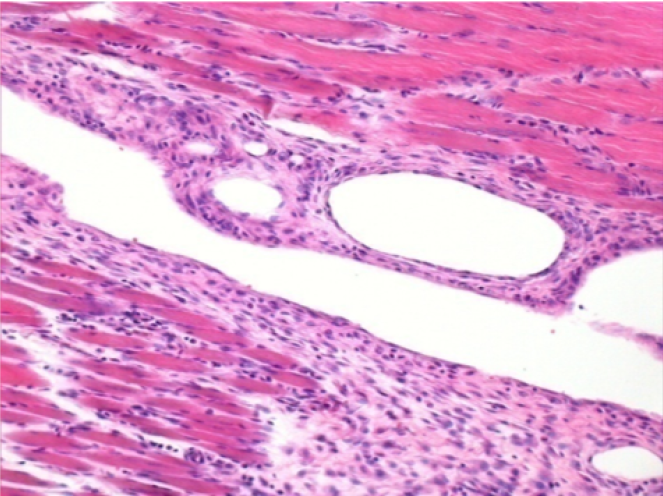

10 días después de la inyección de Endopeel 0,1 ml en el músculo pretibial derecho.

Aquí puede ver la formación de las vacuolas que están rodeadas de linfocitos. Las vacuolas son diferentes a la necrosis tisular. La presencia de linfocitos está relacionada con la permeabilidad de las membranas celulares.

07